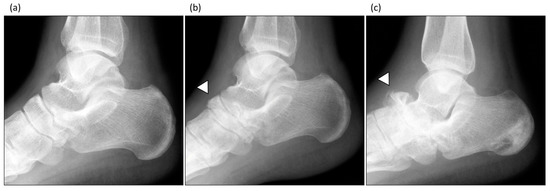

2.7. CN Diagnosis and Treatment